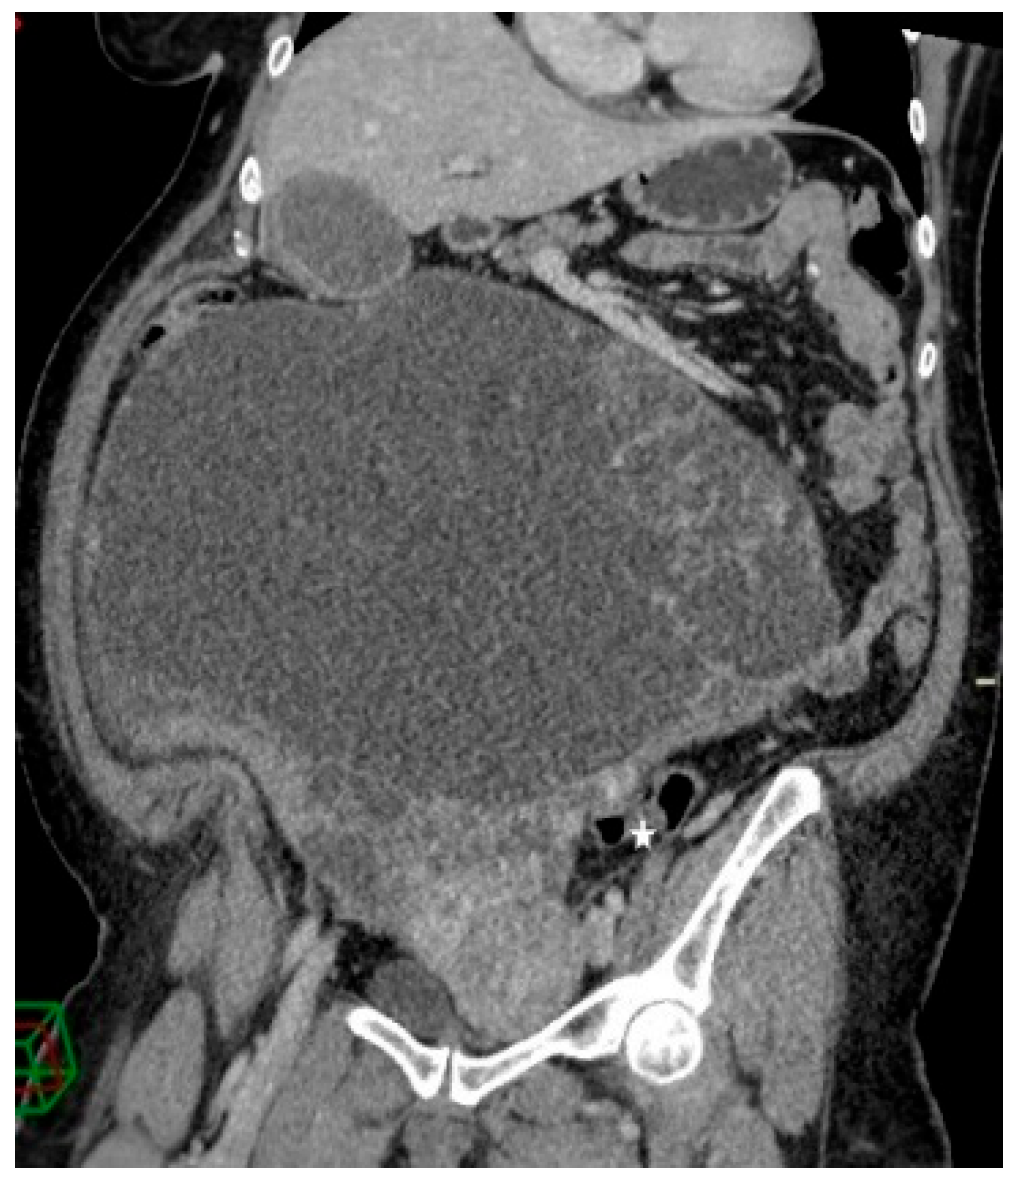

A 68-year-old female patient was admitted to our department due to increasing symptoms of abdominal bloating over the past four months. Other symptoms associated with ovarian cancer were denied by the patient. The patient’s medical history included surgery due to a rupture of an ovarian cyst, while a right adnexectomy was performed 43 years ago. Further, she had hypertension and glaucoma after antihypertensive therapy (Presolol, Asupt, Xalacon). Preoperative CT examination of the abdomen and pelvis confirmed the presence of a tumor in the abdomen and pelvis with a diameter of 335 mm × 275 mm × 345 mm. According to the CT features, the tumor was displacing the surrounding structures, albeit without signs of their infiltration. Initially, the tumor corresponded to left ovarian cystadenocarcinoma (Figure 1, Figure 2 and Figure 3). No intraluminal pathological changes were detected during upper flexible endoscopy and colonoscopy.

Figure 3.

Contrast-enhanced abdominopelvic CT—curved reformation shows a large abdominopelvic cystic multiseptated mass, with a mass effect on the sigmoid colon (white star).